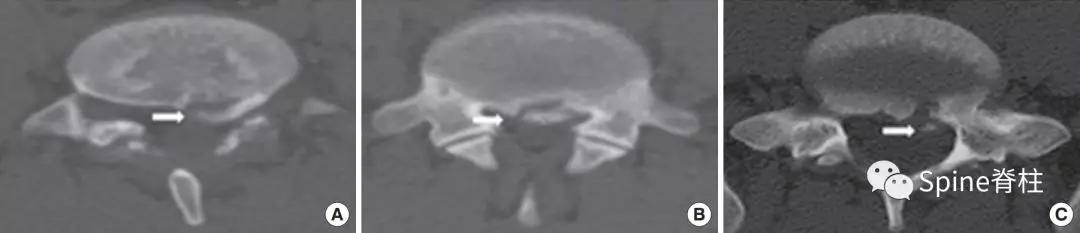

图:箭头所指为离断的椎体后缘

CT是诊断最有效的检查手段

- PARS的Takata分型:

图:A 型为分离部分含皮质骨,不伴椎体后方骨缺损(图A);B 型为分离部分较大,含皮质骨和松质骨,伴椎体后方较大骨缺损(图B);C 型为分离部分较小,含皮质骨和松质骨,伴椎体后方较小骨缺损(图C)。

由于对 腰椎椎体后缘离断症 (陈仲强)发生机理认识各异,有学者认为与青少年骺环未闭及运动创伤导致的椎体及骺环应力较大有关,也有学者认为是一种骨坏死,故命名尚未统一。